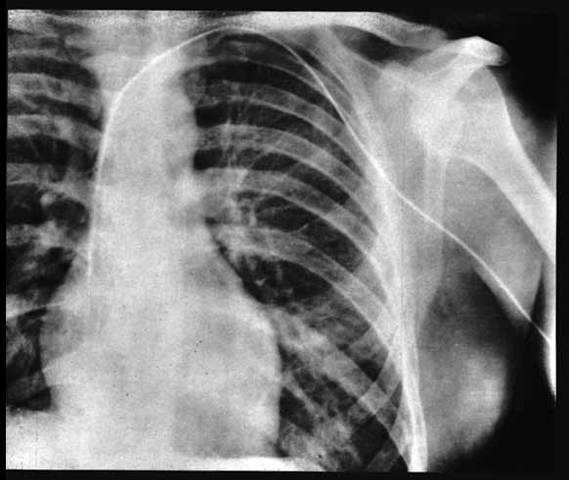

El Dr. Werner Frossman, proveniente de Alemania es el primero en documentar un procedimiento de tal tipo: Él mismo se inserta un cateter a través de la vena antecubital hasta la aurícula derecha, documentándola a través de una radiografía. Su objetivo era la aplicación de fármacos y medio de contraste de manera más efectiva y segura en la auricula cardiaca.